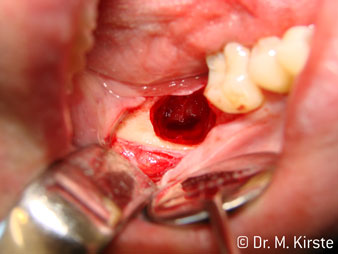

Die Winkelwahl des 45° Handstücks bringt viele Vorteile in der Anwendung. Chirurgisch tätige Kollegen, und für diese ist das Handstück in erster Linie entwickelt worden, werden schnell bemerken, dass man sehr gezielt arbeiten kann. Insbesondere bei der Weisheitszahnentfernung (Abb. 2) bedarf es keiner großen Weichteilabspreizungen im Wangenbereich (Abb. 3). Die Handstückkopfgestaltung kombiniert mit leichten Kopfdrehungen bei der Präparation lassen ein sicheres und schnelles Arbeiten im retromolaren Bereich zu.

Abb. 3